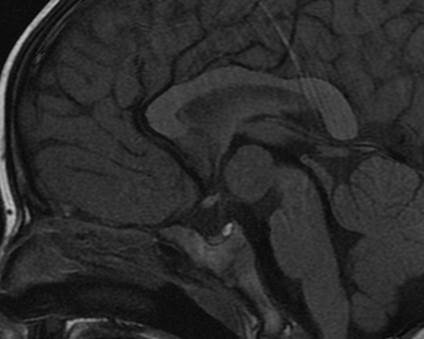

MRI Brain:

There is a 1.5 x 1.7 x 1.7-cm mass centered at the level of the floor of the third ventricle in the region of the tuber cinereum. The signal of the mass follows gray matter on all pulse sequences and there is no associated enhancement on post contrast images. The optic tracts are located just lateral to the mass on each side and the mammillary bodies are located just inferior to the mass.

There is no diffusion abnormality. No evidence of intracranial hemorrhage. No hydrocephalus. The major intracranial flow voids are intact. There is no abnormal enhancement identified. The hippocampal formations appear normal with no evidence of mesial temporal sclerosis. The sulcal and gyral pattern appears symmetric and within normal limits. No evidence of a migrational abnormality. The posterior fossa structures appear normal.

Impression:

Mass at the floor of the third ventricle centered at the tuber cinereum of the hypothalamus, most likely a hamartoma.